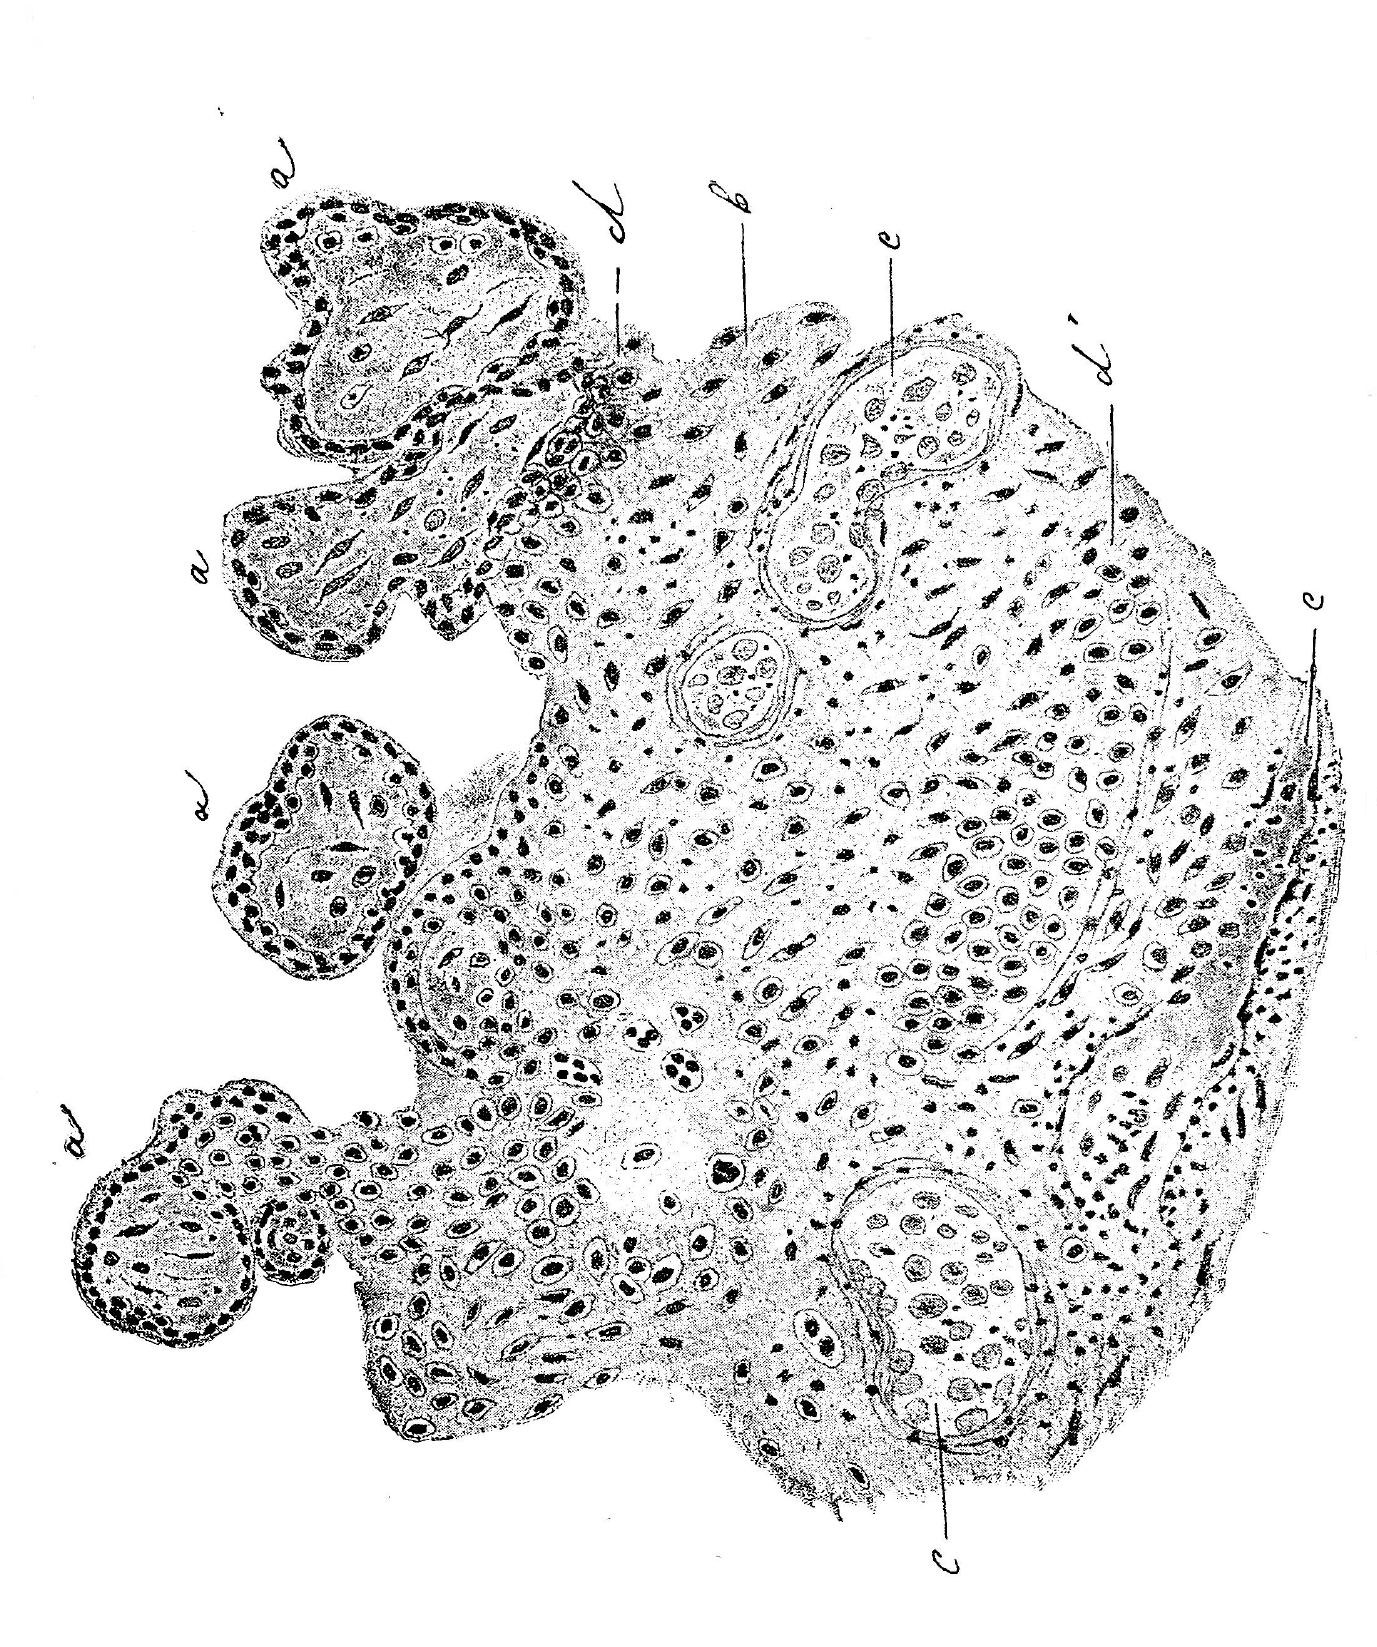

Теперь не трудно понять способъ соединенія placent’ы съ decidua. По мѣрѣ приближенія къ decidua uterina, какъ видно на препаратѣ (рис. 11), decidua foetalis разростается все болѣе и болѣе и, наконецъ, вторгается въ decidua uterina различной толщины отрогами, иногда далеко заходящими въ послѣднюю. Такимъ образомъ, и здѣсь, какъ у человѣка, въ сліяніи яйца со стѣнкой рога активная роль выпадаетъ на долю ворсистой оболочки. Теперь разсмотримъ дальнѣйшую судьбу отростковъ deciduae foetalis въ decidua uterina.

Рис. 11. Subplacenta съ placent’ою: а—часть послѣда съ его ворсинками, b—subplacenta, с мѣсто сліянія placent’ы съ subplacent’ою, d—decidua foetalis, e—decidua uterina, f—материнскіе капилляры.

Figure: 11. Subplacenta with placent: a — part of the placenta with its villi, b — subplacenta, with the placent's fusion with subplacent, d — decidua fetalis, e — decidua uterina, f — maternal capillaries.

Вдаваясь въ decidua uterina они достигаютъ обыкновенно материнскихъ капилляровъ и нерѣдко встрѣчаются такія картины, что ткань decidua foetalis замѣщаетъ собою въ какомъ либо мѣстѣ капилляра бывшій здѣсь эндотелій. Раздвинутая и сдавленная ткань deciduae uterinae претерпѣваетъ регрессивный метаморфозъ: клѣтки ея сдавливаются, появляется инфильтратъ мельчайшими зернышками и лимфоцитами. Но самымъ существеннымъ измѣненіямъ подвергается сама decidua foetalis. Клѣтки ея, будучи ранѣе тѣсно спаянными между собою, начинаютъ отдѣляться одна отъ другой. Такія картины наблюдаются прежде всего въ центральныхъ отдѣлахъ разрощенія (рис. 12). Освободившіяся клѣтки принимаютъ шаровидную или овальную форму, далѣе тѣло ихъ распадается и ядра становятся свободными.

Рис. 12. а—полости, образуемыя распадающеюся decid. foetails или эктодермическими разрощеніями, b—decid. uterina, с—материнскіе капилляры.

Fig.: 12. a — cavities formed by the decaying decid. fetails or ectodermic growths, b — decid. uterina, c — maternal capillaries.

Въ дальнѣйшемъ разрушеніе клѣтокъ распространяется на все клѣточное разрощеніе.

Такимъ образомъ, благодаря распаду клѣтокъ dec. foetalis получаются различной величины полости, иногда достигающія огромныхъ размѣровъ, наполненныя продуктами распада клѣтокъ, ядерными шариками, напоминающими эмбріональные эритрокаріоциты, лимфоцитами (одно и многоядерными), обломками клѣтокъ, ядеръ, зернышками и, наконецъ, различной величины гомогенными комками. Самыя периферическія клѣтки deciduae foetalis вытягиваются въ длинныя веретенообразныя клѣтки, тѣсно прилежатъ другъ къ другу и чрезвычайно напоминаютъ собою тотъ syncytium, который покрываетъ подобныя же эктодерміальныя разрощенія въ placent’ѣ. Вѣроятно, источникъ происхожденія ихъ одинъ и тотъ же. Ничего нѣтъ удивительнаго, что при сообщеніи происшедшихъ такимъ образомъ, полостей съ материнскими капиллярами, онѣ наполняются материнской же кровью.

Слѣдовательно, decidua foetalis, разрушая decidua uterina, образуетъ новыя кровяныя полости и тѣмъ самымъ увеличиваетъ кровяное ложе.